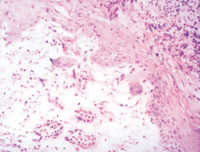

5-2-3 伤后第3天,表皮细胞空泡化,真皮浅层胶原纤维玻璃样变,真皮内散在炎细胞浸润  HE×100